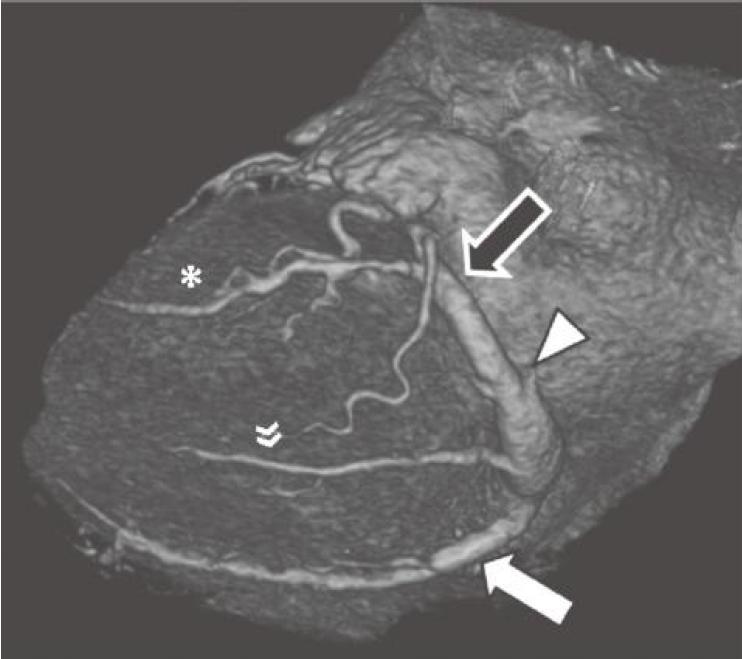

★ 心大静脉走行于左房室间沟(图13-6及图13-7)。

★ 心大静脉汇入冠状窦。

图13-7 心脏左侧面观,心大静脉(黑箭)接收来自左缘静脉(*)的血流。将左心房斜静脉(箭头)与心大静脉的汇合处定义为冠状窦的起点,冠状窦接收来自左心室下静脉(双箭)及心中静脉(白箭)的血流

(五)心中静脉

★ 心中静脉走行于后室间沟(图13-5、图13-7及图13-8)。

★ 心中静脉接收来自心底面以及室间隔大部的静脉血流。

★ 尽管心中静脉通常汇入冠状窦,但也可直接与右心房沟通。

(六)心小静脉

★ 心小静脉走行于右房室间沟下部(图13-7及图13-8)。

★ 心小静脉接收来自右心室膈面的静脉血流。

★ 心小静脉汇入冠状静脉窦。

★ 左(或钝)缘静脉最常见,接收左心室前外侧壁的静脉血流,而后汇入心大静脉(图13-6)。

★ 左心室下静脉引流左心室下侧壁,并终止于在冠状窦(常见)或心大静脉(少见)(图13-7)。

★ 左心房斜静脉沿左房下侧壁走行,常位于左肺静脉与左心耳之间。临床上,将左心房斜静脉与心大静脉的汇合处定义为冠状窦起始部(图13-6)。然而,左心房斜静脉是胚胎期左侧上腔静脉系统的残留;因此,可能表现为永存左上腔静脉。